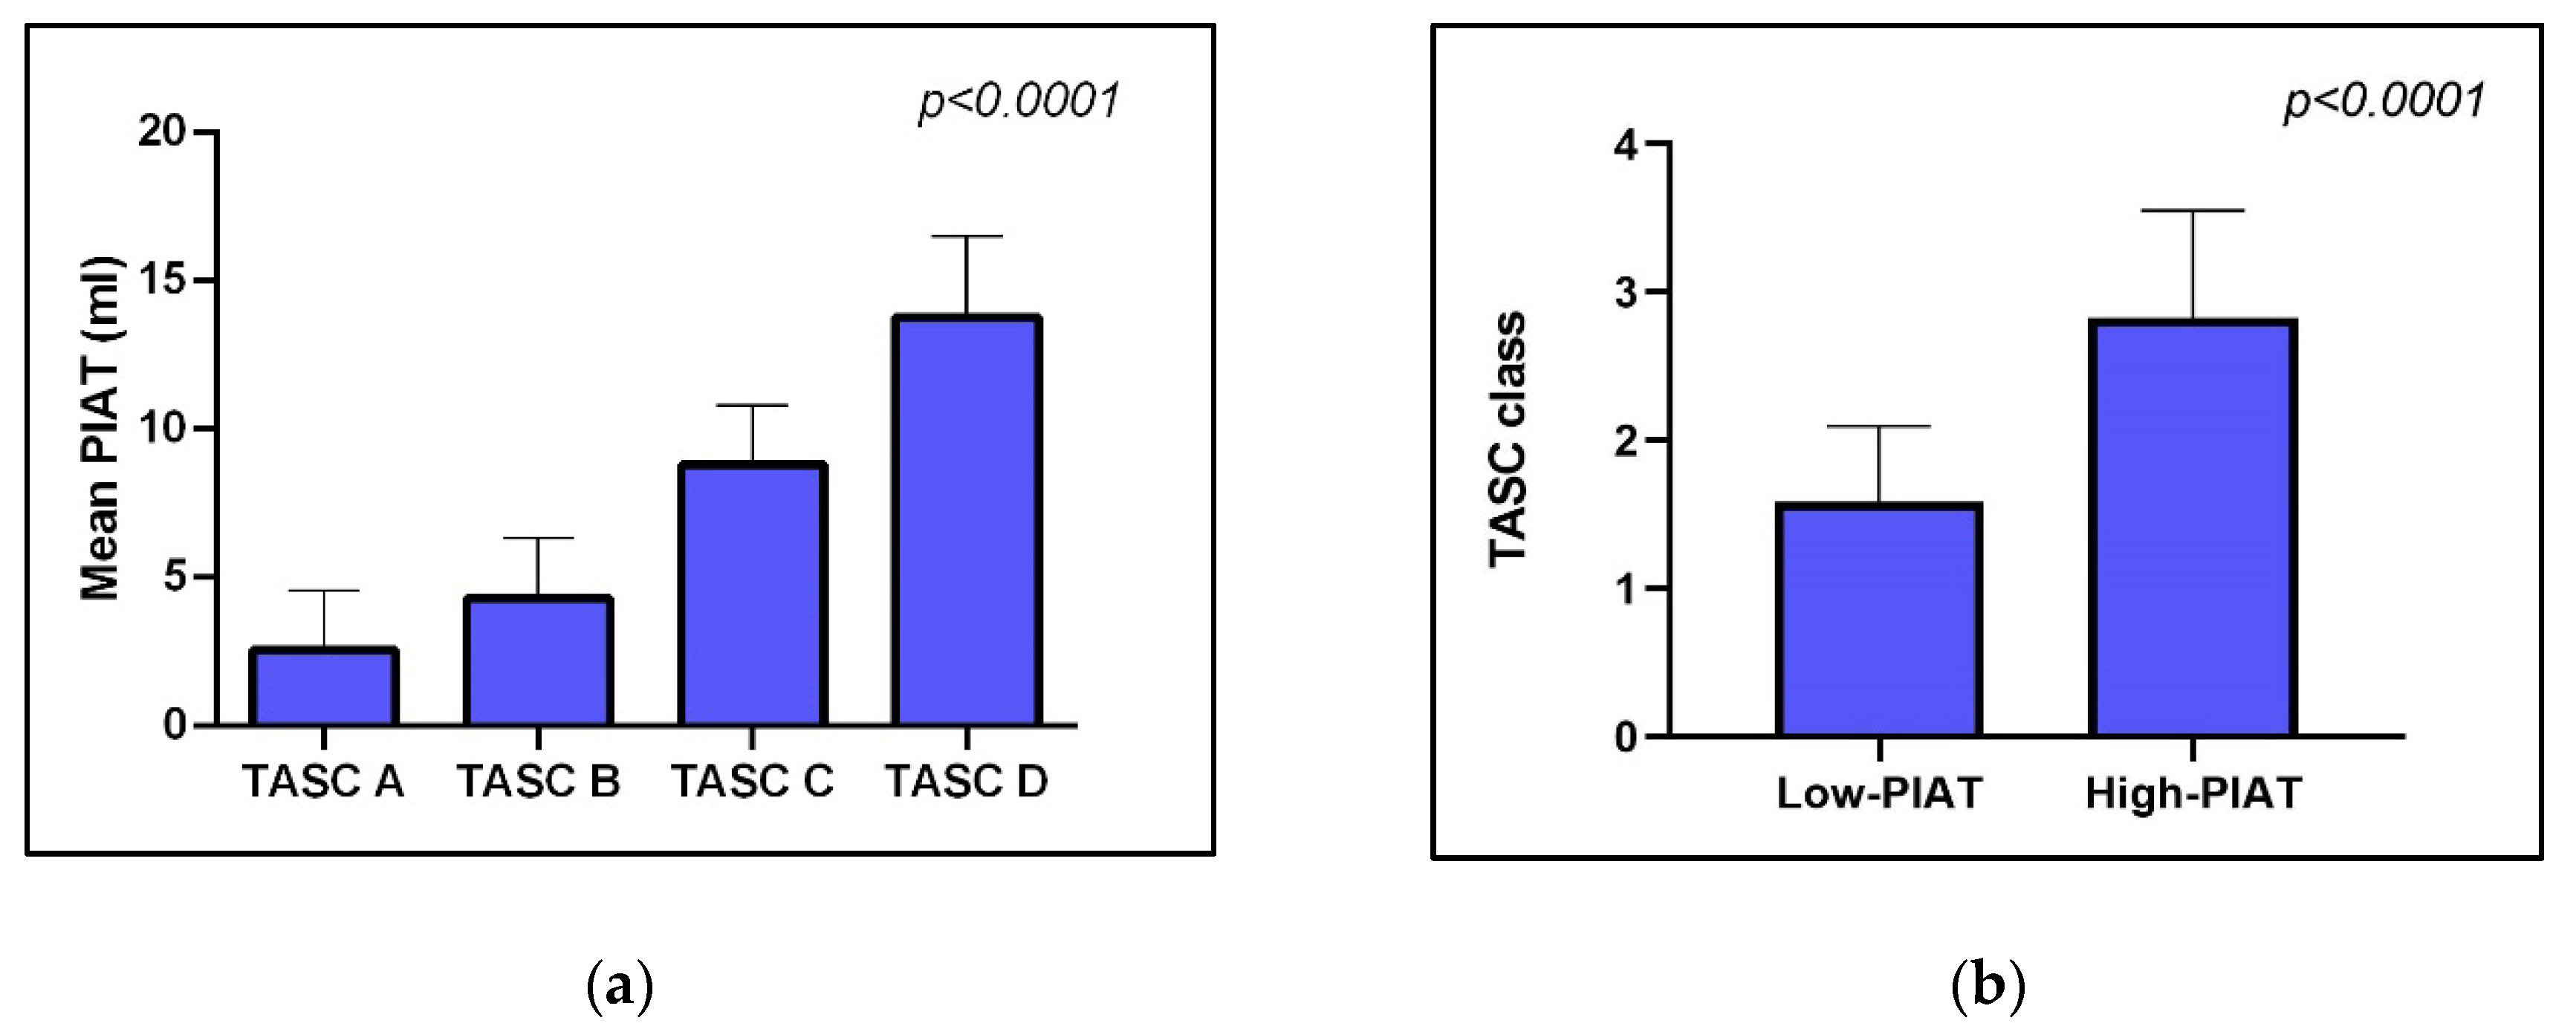

3.2. PIAT Volume and Severity of Peripheral Arterial Disease

| TASC class | TASC A: 7 (41.17%) TASC B: 10 (58.83%) | TASC A: 1 (5.88%) TASC B: 3 (17.64%) TASC C: 11 (64.7%) TASC D: 2 (11.76%) | 95% CI 0.7971 to 1.673 | p < 0.0001 |